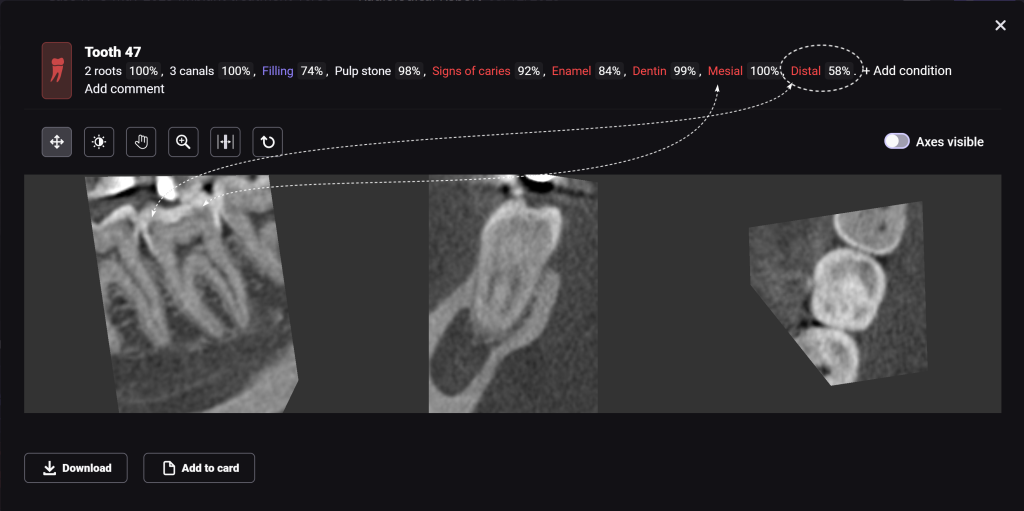

If the probability percentage is over 50%, the teeth are highlighted in red, and the report contains information about the localization and depth of the lesions

The presence of caries on the distal and mesial surfaces of tooth 47 (Universal 31) has been clinically confirmed